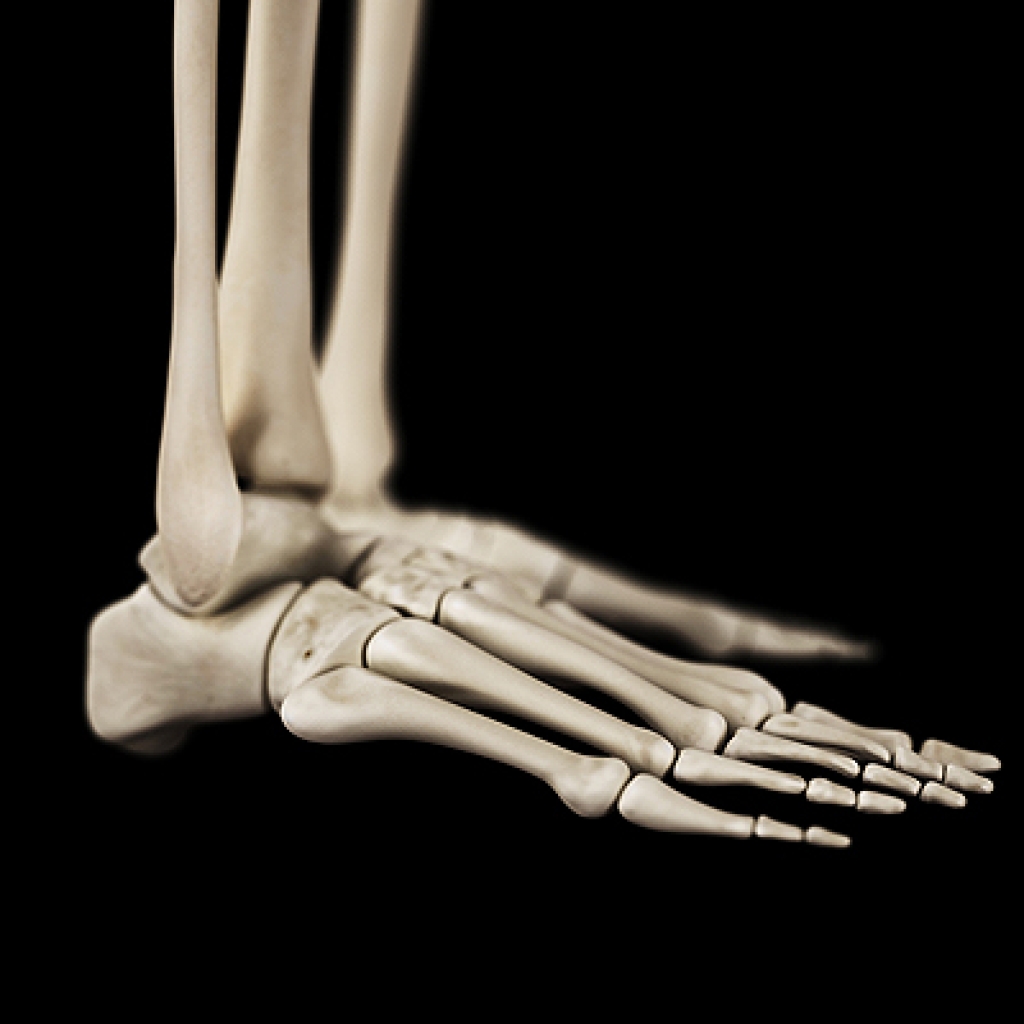

A broken foot is caused by one of the bones in the foot typically breaking when bended, crushed, or stretched beyond its natural capabilities. Usually the location of the fracture indicates how the break occurred, whether it was through an object, fall, or any other type of injury.

Treatment for broken bones varies depending on the cause, severity and location. Some will require the use of splints, casts or crutches while others could even involve surgery to repair the broken bones. Personal care includes the use of ice and keeping the foot stabilized and elevated.